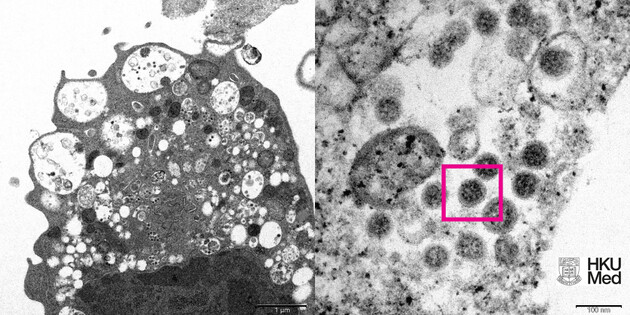

Вчені з Університету Гонконгу показали знімок штаму коронавірусу «Омікрон», зроблений за допомогою електронного мікроскопа. Зображення було опубліковане на сайті університету.

Знімок складається із двох частин. На першій із них (ліворуч) показані клітини нирок мавпи з невеликим збільшенням після зараження вірусом. Так, можна побачити пошкодження клітин з набряклими везикулами, які містять маленькі чорні вірусні частки.

На другій половині (праворуч) можна побачити агрегати вірусних частинок та шипи у формі корони на їхній поверхні.